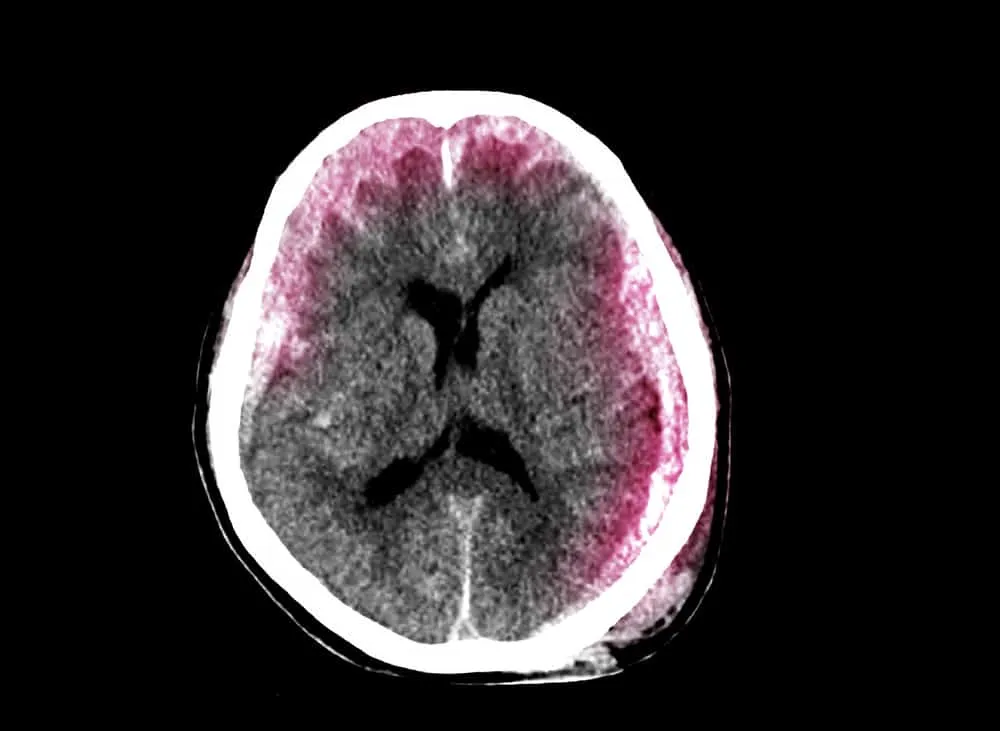

Người bệnh nhập viện sau khi bị chấn thương đầu thường được làm chẩn đoán hình ảnh đầu như chụp cắt lớp vi tính (CT) hoặc chụp cộng hưởng từ (MRI). Những kiểm tra hình ảnh này có thể giúp bác sĩ phát hiện sự tồn tại của tụ máu dưới màng cứng. Chụp MRI ưu thế hơn một chút so với chụp CT trong khả năng phát hiện tụ máu dưới màng cứng nhưng chụp CT lại nhanh và thường sẵn có hơn.

Não của con người được bao bọc bởi các lớp màng não, bao gồm màng cứng, màng nhện và màng mềm, sau đó mới tới xương sọ và da đầu. Khi mắc bệnh tụ máu dưới màng cứng (hay còn gọi là xuất huyết dưới màng cứng), máu sẽ bị tích tụ ở khoảng trống ở giữa màng cứng và màng nhện.

Bệnh có thể cấp tính (khởi phát nhanh) hoặc mạn tính (tiến triển từ từ). Tụ máu cấp tính hoặc quá lớn có thể gây tăng áp lực nội sọ, dẫn đến chèn ép và tổn thương mô não. Tình trạng này có thể đe dọa tính mạng người bệnh.